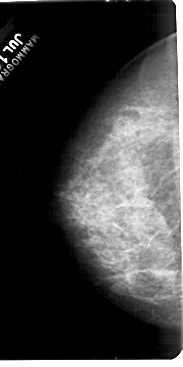

A_1555_1.LEFT_MLO

LEFT_MLO LINES 5491 PIXELS_PER_LINE 3016 BITS_PER_PIXEL 12 RESOLUTION 43.5 OVERLAY